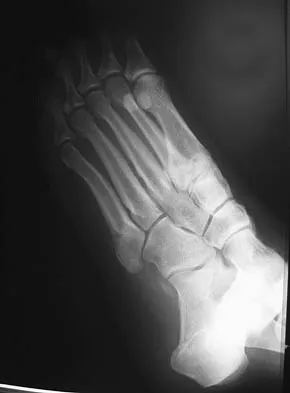

A 13-year-old girl with hallux valgus reports pain after playing basketball. Radiographs show a hallux valgus angle of 20 degrees, an intermetatarsal angle of 11 degrees, a distal metatarsal articular angle of 10 degrees, and a congruent joint. Management should consist of

Explanation

Shoe wear modification is the most appropriate management based on the patient's age, high activity level, and relatively minor symptoms. She also has a mild hallux valgus. Normal radiographic measurements are an intermetatarsal angle of less than 9 degrees, a hallux valgus angle of less than 15 degrees, and a distal metatarsal articular angle of less than 9 degrees. Surgical procedures should be reserved for patients with more severe or progressive deformities. Stephens HM: Bunions, in Fitzgerald RH, Kaufer H, Malkani AL (eds): Orthopaedics. St Louis, MO, Mosby, 2002, pp 1510-1519.